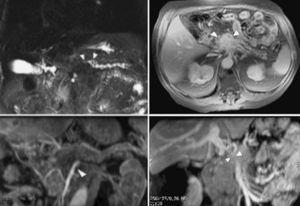

A partir de la complementación de la US con técnica de doppler color ha mejorado el rendimiento de la misma en la evaluación de la extensión tumoral a los vasos arteriales y venosos peripancreáticos, que oscila entre el 84 y el 87%3,4 (fig. 1). Tomiyama et al5 evaluaron la extensión vascular arterial tumoral en 33 pacientes mediante US doppler color, comparando sus hallazgos con los de la angiografía, la cirugía y la pieza de resección. En los 11 pacientes intervenidos describen una sensibilidad del 60%, especificidad del 93% y rendimiento diagnóstico del 87%. En la evaluación conjunta de todos los pacientes incluidos en el estudio concluyen que la US doppler color ofrece un rendimiento diagnóstico superior al de la tomografía computarizada (TC) (72%) y similar al de la angiografía (91%). No obstante, el escaso número de pacientes con correlación patológica supone, en cierto modo, una limitación a las conclusiones de los autores. Hasta donde hemos podido revisar Minnitti et al6 presentan los mejores resultados publicados por el momento, detectando el adenocarcinoma pancreático mediante US en 61 de los 64 pacientes incluidos en su estudio (95,3%), y obteniendo mejores resultados que la TC helicoidal, cuyo índice de identificación tumoral fue del 89,1%. El tamaño promedio de los tumores detectados en la US fue de 3,2 cm (rango: 1,5-6,8 cm), aunque los autores no presentan la correlación patológica del tamaño tumoral medido en la pieza quirúrgica en los 18 casos en los que se pudo llevar a cabo la resección radical del tumor. Los autores presentan un índice de predicción de resecabilidad del 81,4% para la US, algo inferior al obtenido por la TC (86,0%), calculado sobre los 43 pacientes laparotomizados de la serie. Sin embargo, estos buenos resultados no han sido refrendados en la literatura por otros autores hasta el momento.

Fig. 1.--Ecografía abdominal. (A) masa hipoecoica de 8 4, 5 cm en la cola del páncreas, en íntimo contacto con la vena esplénica (2). (B) Estudio doppler color y pulsado que demuestra la permeabilidad de la vena esplénica con un registro sin alteraciones.